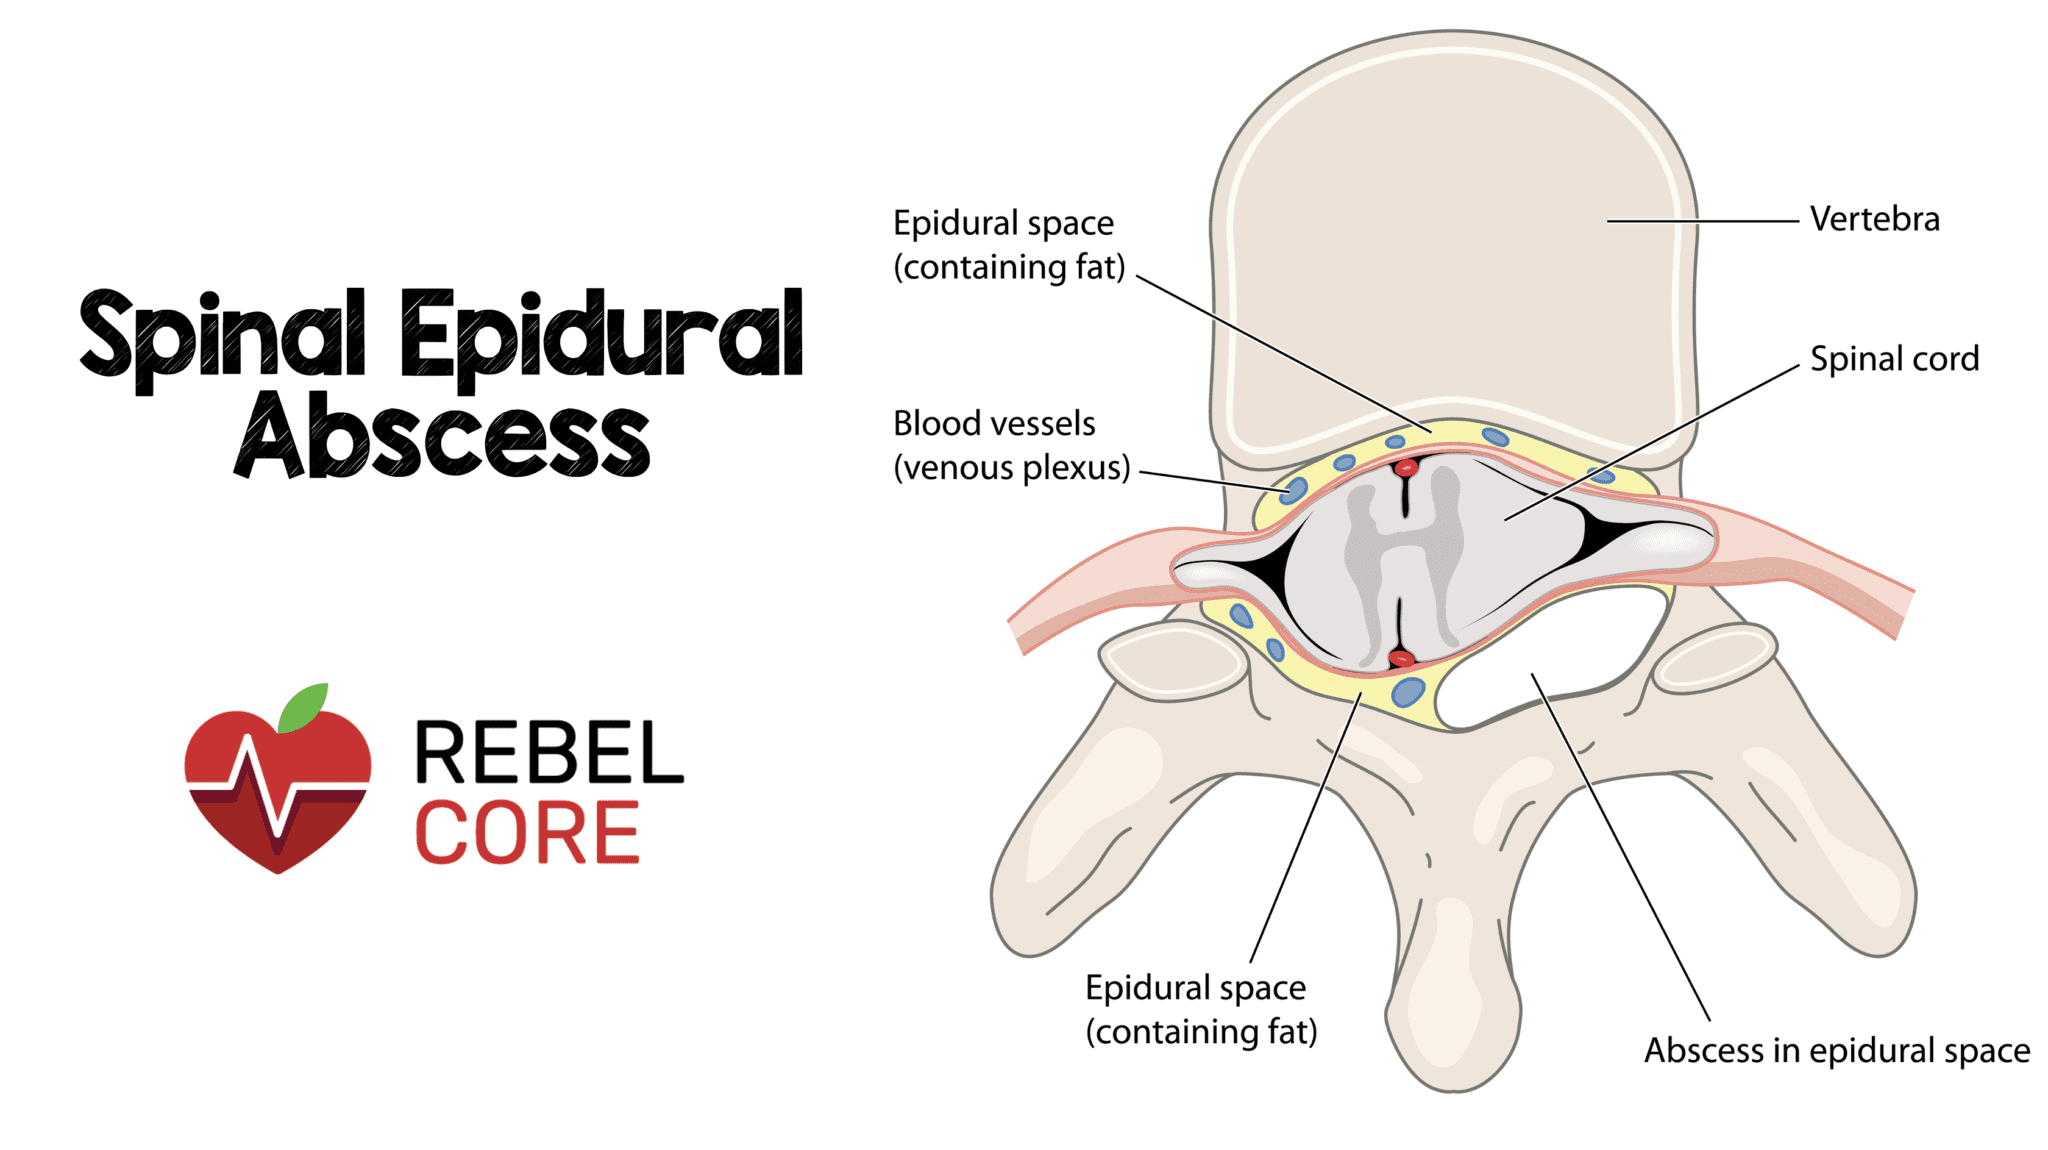

Phlegmon is an area of inflammation in the tissues while an abscess is a little bag of pus that’s more contained The way they’re treated is a different too This article will discuss a. Phlegmon is a medical term describing an inflammation of soft tissue that spreads under the skin or inside the body

It’s usually caused by an infection and produces pus Phlegmon is an area of soft tissue or fluid density effacing or displacing usual fat or other connective tissue and shows variable enhancement However, an abscess typically has a. A phlegmon is a localized area of acute inflammation of the soft tissues

A phlegmon results when an acute infection is not confined as in the case of abscess

Instead the infection spreads along tissue planes and between muscle fibers. Phlegmon is a serious skin infection that affects the soft tissues, leading to inflammation and a collection of pus It is often caused by bacteria entering the skin through a. This article explores the causes, symptoms, diagnosis, and treatment of phlegmon, including its classifications based on clinical course, severity, location, cause, pathogenesis,.

Phlegmon is an unpleasant infectious disease manifested by inflammatory deposits, especially on the skin of a person What is the cause of phlegmon, its first symptoms and. Phlegmon is a type of deep tissue infection that can occur in various parts of the body It can manifest in different forms depending on the location and underlying cause